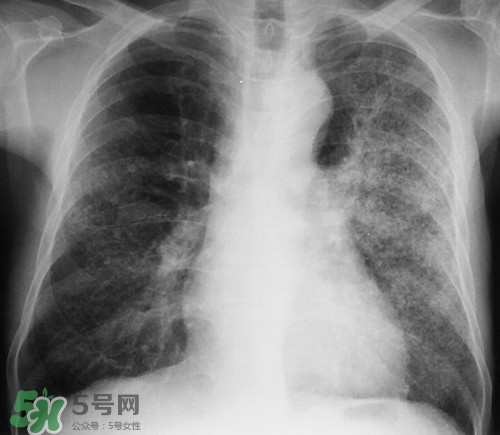

肺炎是常見的呼吸道感染疾病,這病也確實麻煩,如果處理不當(dāng)可能危及生命哦,那么肺炎會不會傳染呢?吃什么好的快呢?下面我們來介紹下吧!